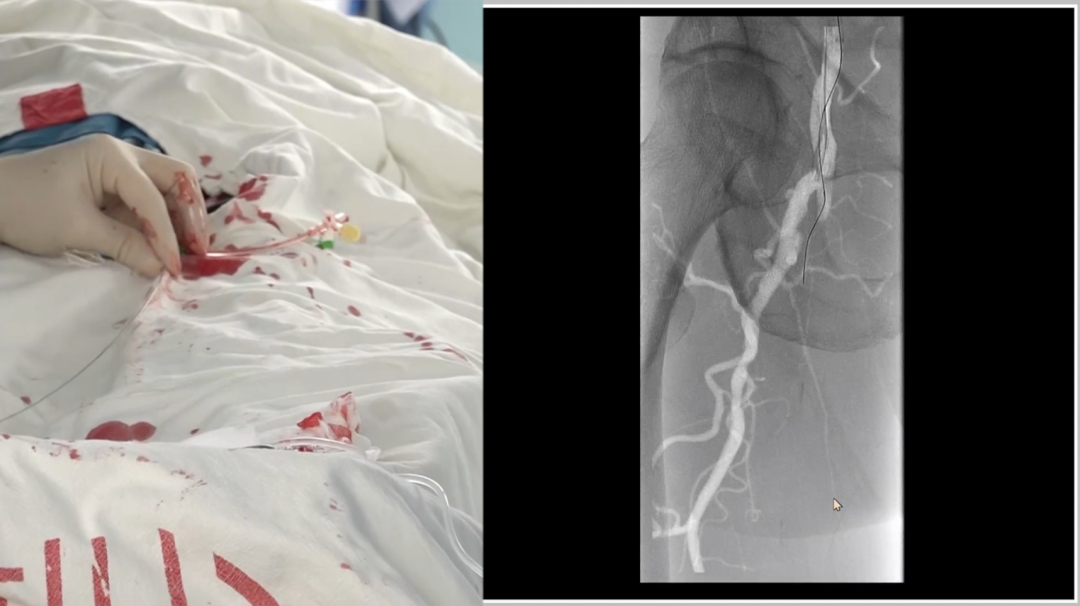

远端困境:

内膜下难以返回真腔,果断选择逆穿

导丝进入远端内膜下后,反复尝试返回真腔失败。为避免过度操作损伤远端流出道,团队决定行逆向穿刺(逆穿):

调整球管至左前斜20°~30°,在路图下定位穿刺点;

近端推注造影剂,透视下确认血管位置,穿刺成功(可见明显充盈缺损);

跟进V18导丝突破远端纤维帽,配合支撑导管完成对接。

逆穿的难点在于选择合适的对接位置,对接判断要点是导丝成袢后,通过近端Terumo导丝触碰,若有明显"碰触感",提示位于同一内膜下,可确认对接。